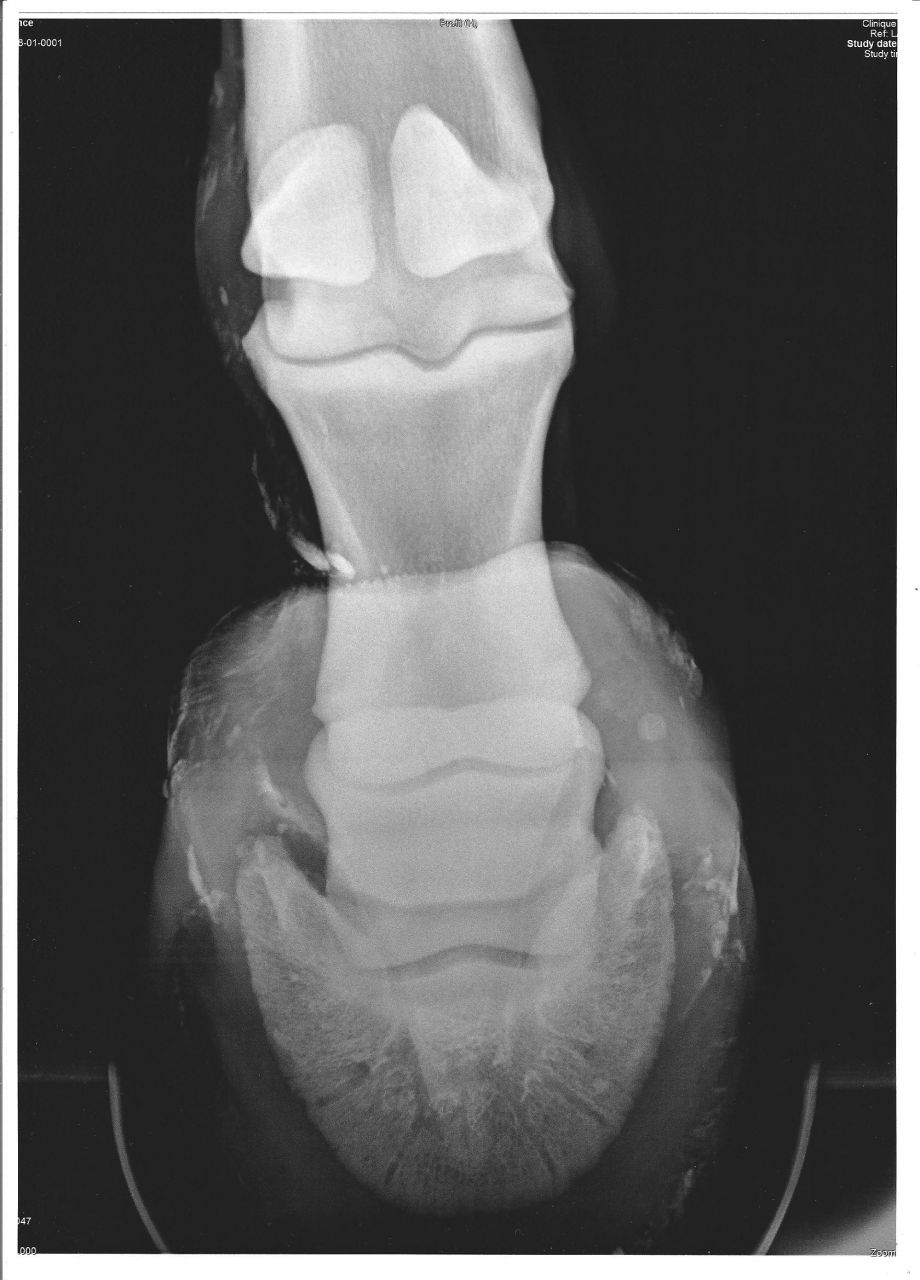

| Dire merci | Bonjour, Mon loulou se remet d'une fracture du processus palmaire ( on suppose que çà fait 3 mois qu'il se l'ai fait et je l'ai découvert par hasard en faisant une radio pour vérifier sa tarre car il boitait il y a 3 mois ). Sa boiterie ne venait pas de là, il s'était coincé le garrot, l'ostéo est passé, problème de boiterie réglé... Le MF m'a dit que çà ne l'empêcherai pas d'être monté par la suite ( même si la fracture ne se ressoude pas... ) J'ai pas encore fait de radios pour vérifier que ce se soit ressouder ou non... Je recherche des cas comme le mien ( surtout l'après fracture, ressoudé ou non ) pour savoir ce qu'il pourrat faire ou non ( ballades, petit TREC pas en compet, petit obstacles, dressages... tous çà pour le plaisir, régulièrement mais pas intensif ) Je ne voudrai pas lui faire faire quelque chose qu'il ne peut pas... J'ai pas encore vue mon véto, c'est les congés... Merci d'avance pour vos réponces |

| Dire merci | Personne a ou connais un loulou avec cette fracture ? J'ai vue mon véto : Même si la fracture ne se ressoude pas, retour à une activité normale après une remise en route ( obstacles... ) Il y a sans doute pleins de chevaux avec cette fracture et qui ont une activitée normale et même il doit y en avoir pas mals que le propriétaire ne sait même pas qu'il a çà car si on ne fais pas une radios du pied, on ne le voit pas car ce n'est pas douloureux et ne provoque pas de boiterie... Du coup, ils n'ont pas de vraies connaissances sur cette fracture... ils savent juste que çà ne fait pas boité et que ce n'est pas douloureux... Mais je vais quand même chercher et demander du côté de MF podologues... |

| Dire merci | J'ai une propriétaire qui a une jument qui a ça, la fracture est passée inaperçue, la jument n'a même pas boitée, elle a été constatée par radio suite à visite d'achat. Elle a une ferrure qui favorise le rolling du pied, sinon elle a une activité normale de cheval de loisir, elle saute très peu par contre, pour la préserver, mais une fois de temps en temps elle fait de l'entrainement TREC sur des hauteurs raisonnables. Après à la visite véto le pronostic était réservé, à savoir qu'à long terme la jument pourrait peut être boiter si jamais une des phalanges se fracture (plus grave). Mais bon y'a même pas 1 "chance" sur 10... |

| Dire merci | Merci à tous ! Je désespérait... depuis mai 2012... Depuis, sa fracture devrait être ressoudée... Je suis entrain de me demander si la dent de loup ( à gauche aussi ) ne serrai pas aussi en cause... tous les soucis qu'il a sont sur la gauche... En plus, son ancienne proprio, lui mettait un mors en 115, alor qu'il lui faut du 135, quelle douleur il devait avoir dans la bouche entre la dent de loup et le mors trop petit ! Et en plus, je n'ai pas penser dessuite à vérifier la taille du mors, vue qu'elle m'avait donner sont fillet... déjà un souci de résolu, reste les autres...julot: Sa fracture s'est ressoudée ou pas ? J'ai oublier de mettre les radios... Je n'ai pas fait faire de radios de contrôle car mon véto m'a dit que dans tous les cas ( ressoudé ou non ), çà ne changerai rien... mais j'envisage de lui faire faire une radio de contrôle, je lui ferrai faire en même temps que sa dent de loup... ![]() |

| Dire merci | Oui ça s'est ressoudé, en fait à la radio la fracture était déjà ressoudée. |